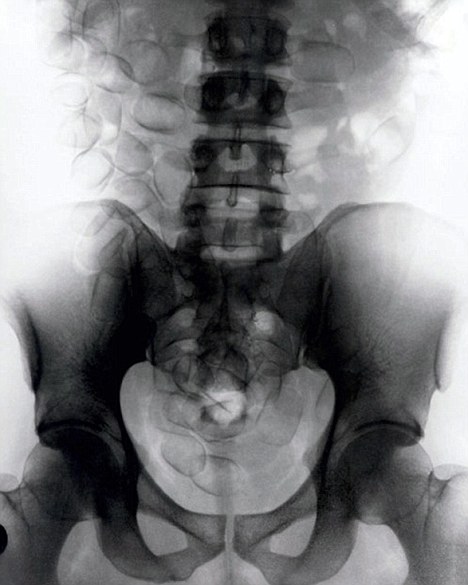

現(xiàn)年30歲的菲達(dá)利斯(Fidelis Ozouli)冒著生命危險(xiǎn)將重達(dá)1公斤的毒品吞下,被抓后卻辯稱不知道吞下的是毒品。當(dāng)時(shí),曼徹斯特機(jī)場(chǎng)的海關(guān)人員看到毒販菲達(dá)利斯臃腫的肚腩,顯得很不自然,于是開(kāi)始懷疑。檢查人員用X射線機(jī)照他的胃部時(shí),發(fā)現(xiàn)了大量可卡因。目前他已被送往附近醫(yī)院,以確保排出所有的毒品。